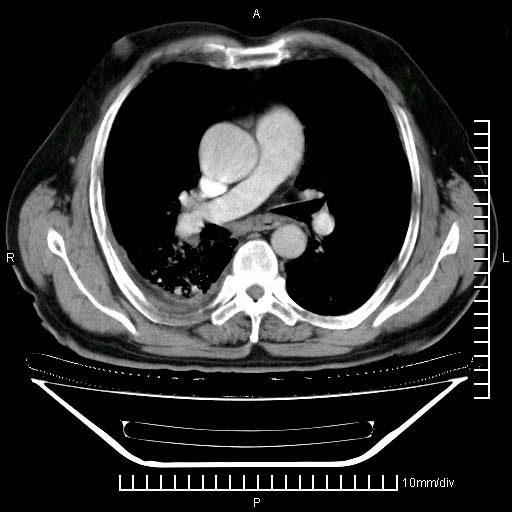

标题: CT24043:胸部增强:男性,60岁

既往肺结核,近10几天,咳嗽,咳痰,右侧胸痛,疼痛较明显,右上肺斑块考虑结核灶胸膜粘连,增强,可惜动脉期没有定好,未见强化,可延迟4分后又见较明显强化,中心见低密度影,如果说结核是边缘强化,可这个灶强化的面积挺大的,让人很挠头。

强化的组织可能是膨胀不全的肺组织或炎性肉芽组织。

1)两肺继发性肺结核。2)右侧胸膜增厚+少量胸腔积液。